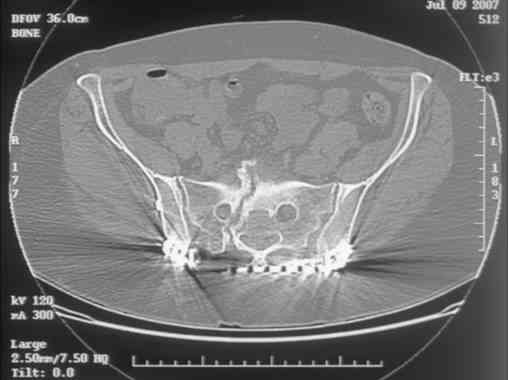

Re: Sacral Non-Union

Chip Routt 23 Август 2007, 23:06

Maybe remove the disengaged iliosacral screw first to see if she improves?

I can't see the axial CT images well enough to detail the potential sacral issues....can you magnify them?

David Zamorano 25 Август 2007, 21:05

Here is a magnified view. Sorry about the quality but the CT was scanned into our system.

dave

Отправитель: Chip Routt 25 Август 2007, 21:08

Thank you...it might help to remove the disengaged and other iliosacral screws then insert longer lag screws into the upper sacral segment and if anatomically feasible into the second sacral segment as well.

You could do it percutaneously and even add an electrical stimulation device if that seems reasonable.

At this point, I'd ignore the right pubic root issue if asymptomatic.

If simple measures such as those above fail, then you could remove it all, take down the sacral fracture site, refix with alternate techniques, and bone graft.

Chip